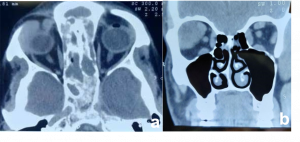

Sub Periosteal Abscess. Coronal contrast-enhanced CT image of right orbit showing extraconal marginally enhancing fluid collections located superonasally, consistent with subperiosteal abscess. These are present in continuation with opacified right ethmoidal air cells and right maxillary antrum with soft tissue density with hyperdense content. |

| Sub periosteal abscess[14] | No age/gender predilection | Collection of subperiosteal fluid causing abaxial proptosis along with other signs of cellutlitis | CT- shows hypodense, convex collection with ring enhancement present along orbital wall